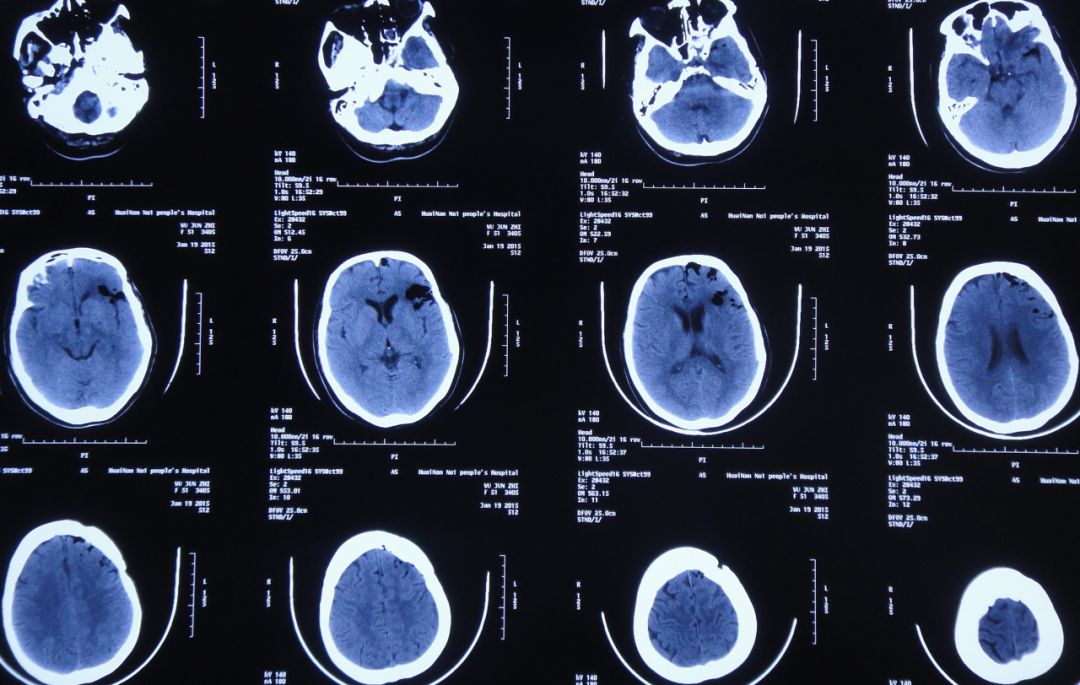

患者女,50岁,安徽省淮北市人。2014年12月14日,患者因高处坠落伤(2米左右)伤及头胸部及四肢,致昏迷,左耳、左鼻流血性液体,急诊前往安徽省淮南市潘集区某医院急查头CT显示左额叶脑挫伤、左侧颞骨凹陷性骨折、脑肿胀、颅内积气(图1);眼眶CT显示双侧眼眶内侧壁骨折(图2);胸部CT显示左侧肋骨骨折伴肺挫伤;右上肢X片显示右桡骨远端粉碎性骨折;左肩部X片显示左侧锁骨骨折。立即给予住院,保守治疗。

图1:2014年12月14日头CT:左额叶脑挫伤、左侧颞骨凹陷性骨折、脑肿胀、颅内积气

入院后第一天即2014年12月15日,患者神清,出现左眼肿胀,视力消失,左眼瞳孔增大,对光反射消失,左侧外耳道见澄清液体溢出,复查头CT:左额叶脑挫伤较前加重(图3)。

图3:2014年12月15日头CT:左额叶脑挫伤较前加重

入院后第二天即2014年12月16日为求进一步治疗,患者被转入淮南市某人民医院,查头CT:左额叶脑挫伤、脑组织弥漫性肿胀(图4);胸CT:双下肺感染(图5)。

图4:2014年12月17日头CT:左额叶脑挫伤、脑组织弥漫性肿胀、颅内积气消失

给予脱水、止血、营养神经、预防感染等保守治疗。之后约20天时间内,患者左耳溢液逐渐停止、左眼肿胀逐渐好转。但至外伤后19天即2015年1月2日,患者坐起后发现左鼻腔流液;复查头CT显示颅内大量积气(图6),给予保守、卧床、抗炎处理。

图6:2015年1月2日头CT:颅内大量积气

2015年1月12日,患者仍有脑脊液鼻漏;复查头CT:颅内积气有所减少(图7)。

图7:2015年1月12日头CT:颅内积气较前有所减少

2015年1月19日,患者仍有脑脊液鼻漏;复查头CT:颅内积气有所减少(图8)。

图8:2015年1月19日头CT:颅内积气有所减少

2015年1月26日转入中煤特殊凿井公司医院,继续半卧位保守治疗,治疗期间患者起床活动后仍有鼻腔流液现象,伴间断头痛。2015年1月30日复查头CT:左额颞软化灶形成,颅内积气明显减少(图9)。

图9:2015年1月30日头CT:左额颞软化灶形成,颅内积气明显减少

2015年5月18日患者因鼻腔流液增多,被转入徐州市某中心医院,头CT显示左额叶软化灶形成,颅内积气(图10)。

图10:2015年5月18日头CT:左额颞软化灶较前减小,颅内积气少量积气